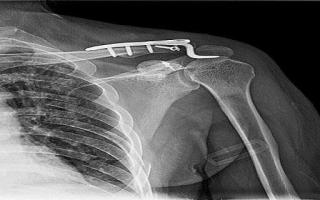

鎖骨骨折は3種類に分類される 鎖骨骨折の保存治療 鎖骨遠位端骨折(外側端骨折)の手術法 鎖骨骨幹部骨折の手術法 鎖骨近位端骨折は珍しい まとめ 鎖骨 は細く弯曲した形状をしているために、 小児から大人まで幅広い年代で骨折を起こしやすい骨 として知られています。 この鎖骨が折れてしまったときの治療法選択においてはいくつか考えるべき要素があり鎖骨骨折の固定期間中のお風呂はどのようにするのですか? 服や下着の着替えやお風呂の際は、鎖骨固定帯(クラビクルバンド)を外す必要があります。 医師の指示に従って、骨折した方の手に負担がかからないようにしましょう。 腕を90度以上に持ち上げたり、骨折している方の手で体を支えたりすることは避けましょう。 服の着替えは、服を着る時は、前開き痛みはいつまで続くの? 治るまでの期間と痛みのピーク 痛みのピークは? 手術と保存加療の違いは? 子供の場合 子供の鎖骨骨折の治療は?

肩鎖関節脱臼 鎖骨骨折 Sports Medicine Library ザムスト Zamst

鎖骨骨折は最も多い骨折の1つであり,特に小児で多い。診断は単純X線による。ほとんどの型は三角巾により治療する。 病因 鎖骨骨折は通常,肩関節の側方から落ちる転倒,または頻度は低いが直接打撃により起こる。 分類 従来から,治療は以下の分類に基づいて行われている。 Class Aの骨折Mixi鎖骨骨折者 会社に復帰するまでの期間は? こんばんは。 トピ立て失礼します 事故で右鎖骨を骨折し、手術で骨に針金のようなものを 通しました。 1週間後退院です。 退院してからどれぐらい自宅で安静にしたほうがよいのでしょうか? 先生に聞いたとこ · 骨折の治癒過程の期間の目安 第1期 骨折血腫期 8~10日 第2期 軟仮骨形成期(壊死組織の除去)10~25日 第3期 骨芽細胞増殖期 ~60日

⑤鎖骨骨折の3%は血気胸や同側の肋骨骨折を合併しているので,注意を要する. 疾患の特徴と読影のポイント 鎖骨骨折 縦隔と重なって判読しにくい時があるので, 圧痛点を中心に注意深く読影すること.矢 印が骨折部. 図1 歳,女性.内側1/3 の骨折 Edinburgh 分類Type 1 A1 図2 66 歳,男性 · 鎖骨骨折はスポーツ復帰までは個人差や競技によっても異なりますが、大体6~12週程度と言われています。 まとめ 鎖骨骨折は骨折全体の15%を占める。 ギプス固定やクラビクルバンドで固定する治療法が多い。骨折後のリハビリは「負傷後数日」もしくは「処置をした後」から 負傷後数日~数週間を「急性期」と呼びます。 治癒にかかる期間 は負傷時の年齢や本来の体力、負傷部位や手術の有無にも左右されますが、一般的に負傷前の状態に戻るまで おおむね3か月~6か月かかると考えられてい

鎖骨骨折のまとめ 鎖骨の解剖 治療 手術適応と治療期間 鎖骨骨折にも色々あります 研修医 救急医のための整形外科 外傷 スポーツ医学マニュアル